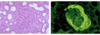

neutrophilic infiltrate, suppurative necrosis, and abscess formation

parenchyma shows interstitial fibrosis with an inflammatory infiltrate of lymphocytes, plasma cells, and occasionally neutrophils

Xanthogranulomatous pyelonephritis - chronic pyelonephritis characterized by accumulation of foamy macrophages intermingled with plasma cells, lymphocytes, epithelioid cells, and occasional giant cells (associated with proteus)